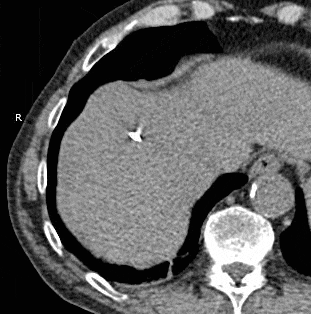

Hepatic cryoablation.gif

Animated GIF showing cryoablation of mass in right liver lobe using two probes. Time elapsed is approximately 30 minutes.